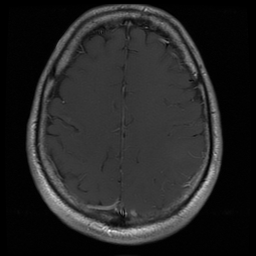

我正在尝试这张图像,来自癌症成像档案馆(TCIA) (256x256):